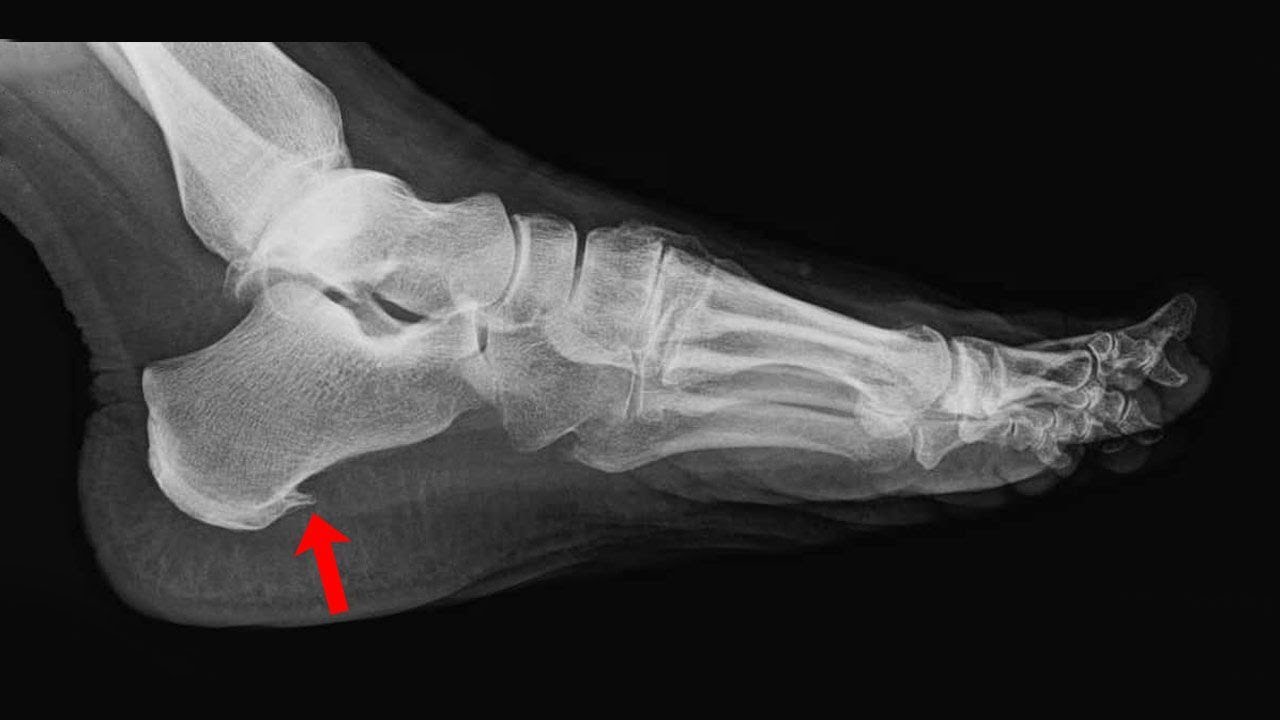

Что такое пяточная шпора (подошвенный фасциит)?

Это костный нарост на пяточной кости, который формируется на фоне хронического воспаления фасции. Но сам нарост обычно не является основной причиной боли.

Как понять, что это именно пяточная шпора?

Типичные признаки — острая боль в пятке при первых шагах, болезненность при надавливании на бугор пятки и усиление боли после нагрузки.